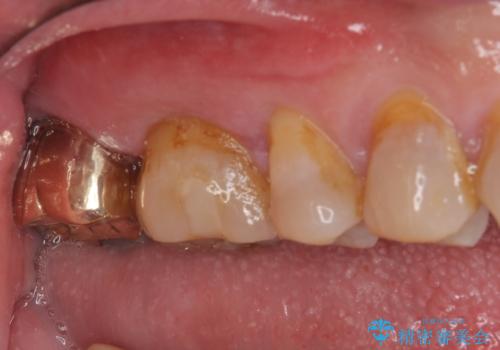

- 銀歯が外れてしまったとのことで来院された患者様です。

上顎奥の粘膜に近い部分で、外れた銀歯の下には大きく虫歯が広がっていました。

虫歯をしっかりと取り除き、ゴールドインレーにて修復することとしました。

ゴールドインレーは銀歯のインレーやセラミックインレーと比べ、「技工操作の精度が高く、適合が著しく良い」というメリットがあります。特に上の奥歯は歯科医師の操作が行いにくいため、「適合の良さ」は再治療のリスクを防ぐ上でとても重要な要素となります。

上の奥歯は金属色が見えることもないため、審美的な問題は全くありません。